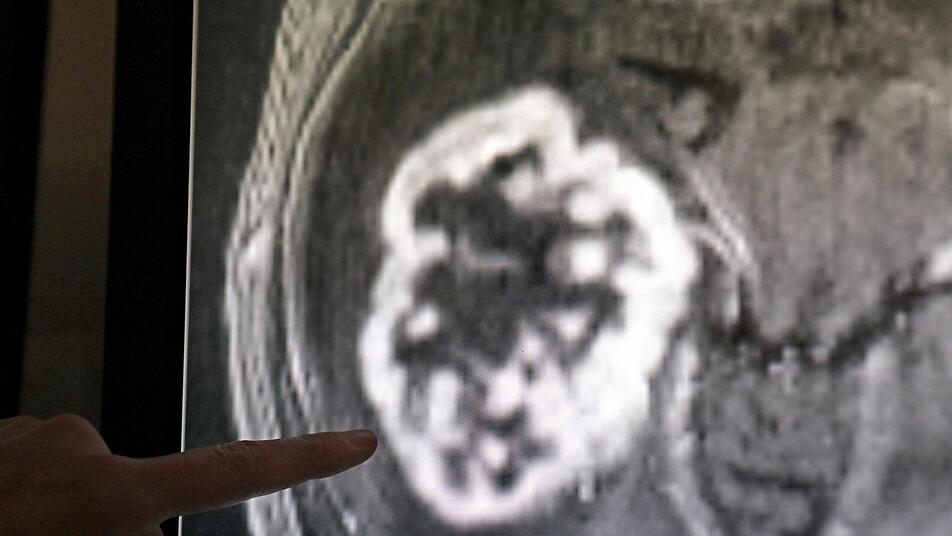

Eine neue Forschungsstudie könnte die Krebsdiagnostik entscheidend vorantreiben. Symbolfoto: Bernd Wüstneck/dpa

"Das Außergewöhnliche ist, wie einige der genetischen Veränderungen viele Jahre vor der Diagnose aufzutreten scheinen", erklärt die an der Forschungsstudie beteiligte Clemency Jolly. Sie arbeitet am "Francis Crick Forschungsinstitut" in London. Die Wissenschaftler haben insgesamt circa 2700 Tumore untersucht. Darunter befanden sich 38 verschiedene Arten von Krebs, beispielsweise aus dem Gehirn oder der Leber.